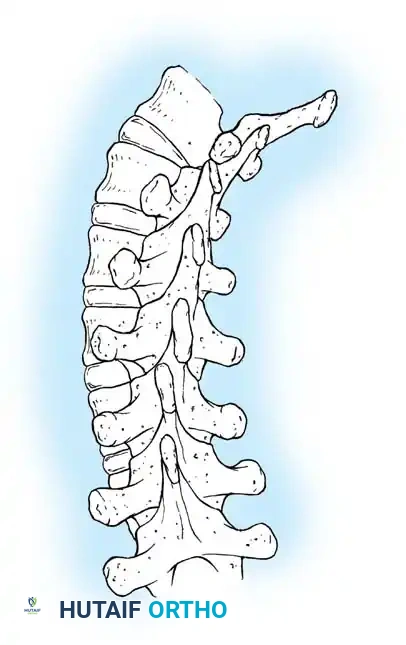

Technique of dual-rod instrumentation showing anteroposterior and lateral views. The construct is carefully contoured to maintain sagittal alignment, with extended tandem connectors placed in the thoracolumbar spine to minimize soft-tissue profile.